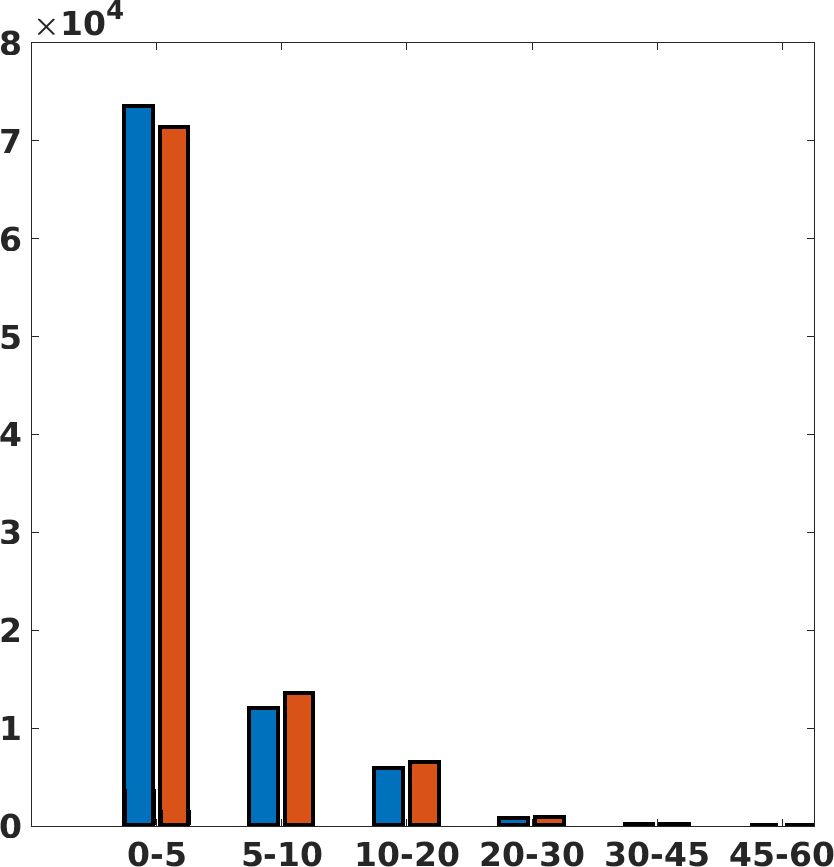

Fig. 7(a-b-c, left) shows the box plot of the statistics of the PSNR on three different anatomical districts, comparing the target images with the prediction and the cubic convolution, respectively. The metrics are computed on a data set of 200 images of the same district and with the same up-sampling factor. We report that the PSNR median value improves of on obstetric 2X raw images, on cardiac 2X raw images, and on abdominal raw 4X images.

Fig. 7(a-b-c, right) shows the histogram of the absolute value of the error with respect to the target image, of the prediction and Cubic convolution results, respectively. The histograms show the number of pixels where the prediction error is lower than 5 (i.e., the first bin of the histogram), which means very similar to the target when visually analysing the images. From the Cubic convolution to the predicted images, this value increases of on obstetric 4X raw images, on cardiac 4X raw images, and on abdominal 4X raw images.